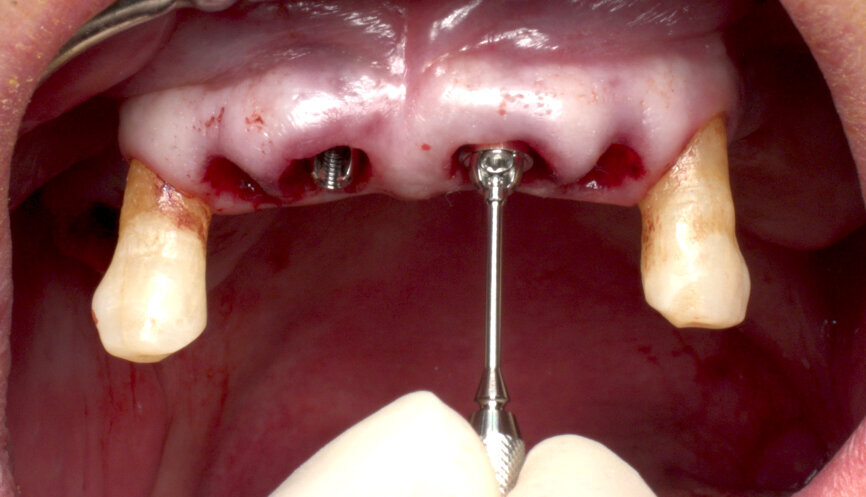

After final implant seating, BLT Type 54 SmartPegs from Osstell were placed on each implant, and the ISQ level was measured and recorded at implant connection level. Values between 75 and 85 out of 100 were obtained, confirming the immediate loading possibility on all the implants (Figs. 7 & 8).

SRAs were connected to all of the implants: two 17º Type A angulated SRAs were placed on the anterior implants to correct the angulation for immediate prosthetic rehabilitation. Straight SRAs were placed on the remaining implants (Fig. 9). New ISQ levels were measured at abutment level using the convenient BLT Type 25 SmartPegs. It is important to record the ISQ level at implant and abutment level in the surgery so that the values can be extrapolated in future Osstell readings at SRA level.